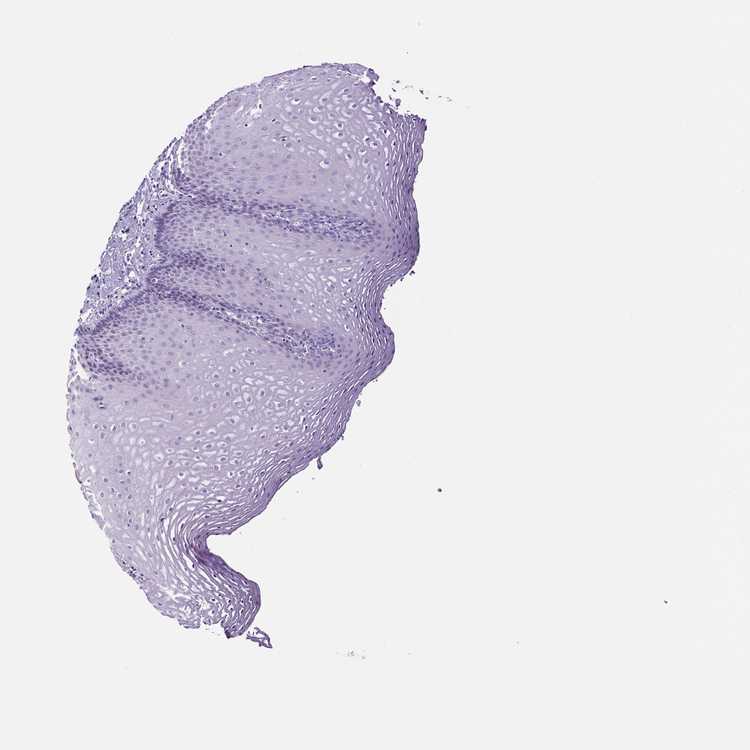

ESOPHAGUS - Antibody stainingi

Antibody staining in the annotated cell types in the current human tissue is reported as not detected, low, medium, or high, based on conventional immunohistochemistry profiling in selected tissues. This score is based on the combination of the staining intensity and fraction of stained cells.

Each image is clickable and will lead to virtual microscopy that enables deeper exploration of all samples and also displays staining intensity scores, fraction scores and subcellular localization as well as patient and tissue information for each sample.

Antibody HPA001042Antibody HPA029543Antibody CAB023669Antibody CAB062562Antibody CAB067751Antibody CAB068229Antibody CAB068230Antibody CAB068231

Squamous epithelial cells Not detectedNot detectedNot detectedNot detectedNot detectedNot detectedNot detectedNot detected